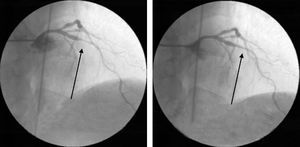

Ad-hoc angioplasty was performed on both vessels with direct stenting (Fig. 2), using standard intracoronary devices (3.0mm×12mm in the proximal LAD and 3.0mm×15mm in the circumflex artery).

Angiographic control of the last lesion treated (proximal LAD) showed a good angiographic result at the stent implantation site, but a new pre-stent lesion was now visible in the proximal circumflex artery (Fig. 3).